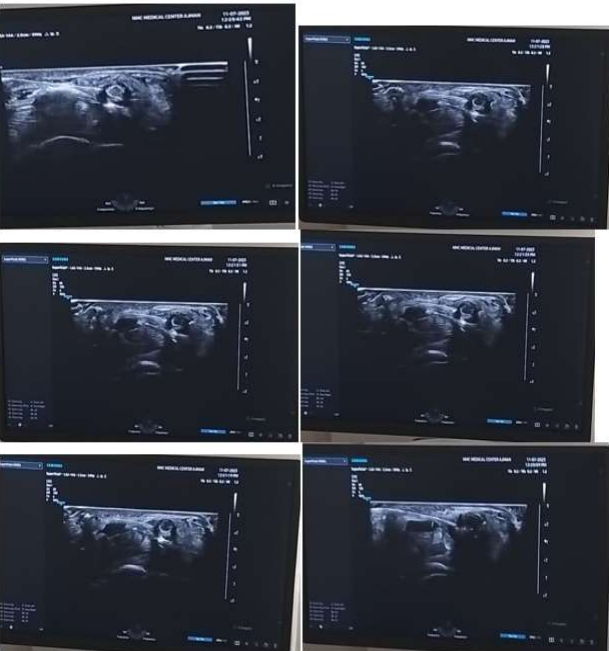

FIG 1. Median Nerve Hydrodissection(HD) at The Wrist Under Ultrasound Guidance.

Figure 2, Figure 3, Figure 4, Figure 5

TOTAL 4 ULTRASOUND GUIDED MEDIAL NERVE HYDRODISSECTION FOR CARPAL TUNNEL SYNDROME WERE DONE BETWEEN JULY 2023- JANUARY 2024.

Technique  used – method 1

Linear probe, high frequency.

25 g needle 1.5” length

Syringe 5 and 10 ml

20-50 ml 5% dextrose

2% lidocaine

Dressing

STEPS-

NERVE IDENTIFICATION- I usually start from proximal to distal from the forearm identifying the nerve ( honey comb appearance) in the forearm and then trace it distally into the carpal tunnel in the wrist.

The nerve is easy to find proximally in the forearm due to absence of any tendons and clarity of the structure within the forearm MUSCLES.

A 360 degree dial needle placement and injectate injection is done to free the nerve from the adhesions all around as shown in the diagram and USG  pictures.

Figure 6, Figure 7, Figure 8

Figure 1

Figure 2

Figure 3

Figure 4

Figure 5